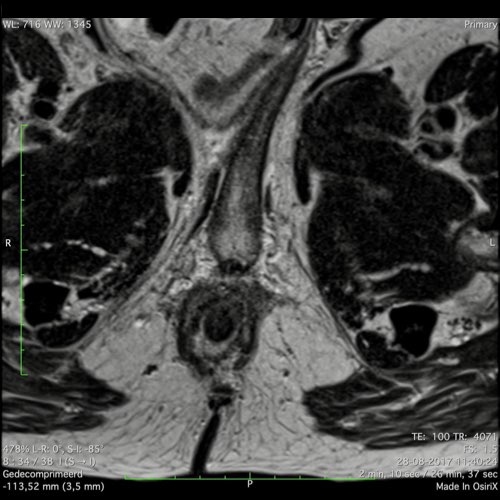

Đặc điểm MRI

- Thường khó xác định

- Thường biểu hiện nhưdày thành ruột lan tỏa, đoạn dài

- Kiểu tăng trưởng dưới niêm mạc, cho ra mộtHình ảnh “bia” (target)trên các hình ảnh cắt ngang

- Thâm nhiễm mỡ trực tràng lan tỏalà phổ biến

Hình ảnh

Các hình ảnh được cung cấp cho thấy ung thư biểu mô tế bào nhẫn với tình trạng dày lan tỏa thành trực tràng, hình ảnh bia bắn điển hình, và sự xâm lấn mỡ mạc treo trực tràng.